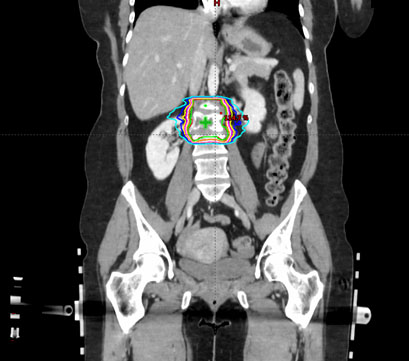

Figure 3. Planning target volume (PTV) and organs at risk (OAR) shown in a CT coronal plane

A young female patient with triple negative breast cancer complained of low back pain. Lumbar spine MRI showed diffuse abnormal enhancement in the L2 vertebral body with mild cord compression and deformity of the vertebral end plates and mild paraspinal extension anteriorly. A CT-guided biopsy confirmed a metastasis in the L2 vertebral body. She was subsequently treated with VMAT spinal SRS using a single fraction of 2400 cGy. For SRS treatment planning, the patient was CT-simulated on an SRS board in a supine position with hands folded across the chest. The planning target volume (PTV) consisted of the L2 vertebral body including bilateral transverse processes, the inferior end plate of the L1 vertebral body, and the superior end plate of the L3 vertebral body, which formed a circumferential PTV around the vertebral foramen (). The organs at risk (OAR) included the bowel, cauda equina, thecal sac, spinal cord, liver, and bilateral kidneys. In addition, a series of optimization structures were also contoured for dose tuning. By assigning proper dose constraints, these tuning structures could drive the higher isodose curves closer to the PTV, thus eliminating the undesirable hot spots in normal tissue and reducing integral dose to the body as well.

Figure 5 shows the dose distribution in a representative coronal plane. The green line represents the 100% isodose line. All the dosimetric parameters met our institutional dose tolerances. In particular, the PTV dose conformity index was 1.04. The PTV V100% was 96%, with a mean PTV dose of 2563.4 cGy. The maximal and mean cord doses were 816.5 and 191.9 cGy, respectively, far below our institutional dose tolerance of 1400 cGy. The VMAT spinal SRS plan was delivered on a Varian TrueBeam machine using a 6X FFF beam with an intra-fractional KV imaging frequency of one image/20°.

Figure 5. The isodose distribution of the VMAT spinal SRS plan. The green line represents the 100% isodose line. It is highly conformal to the shape of PTV.